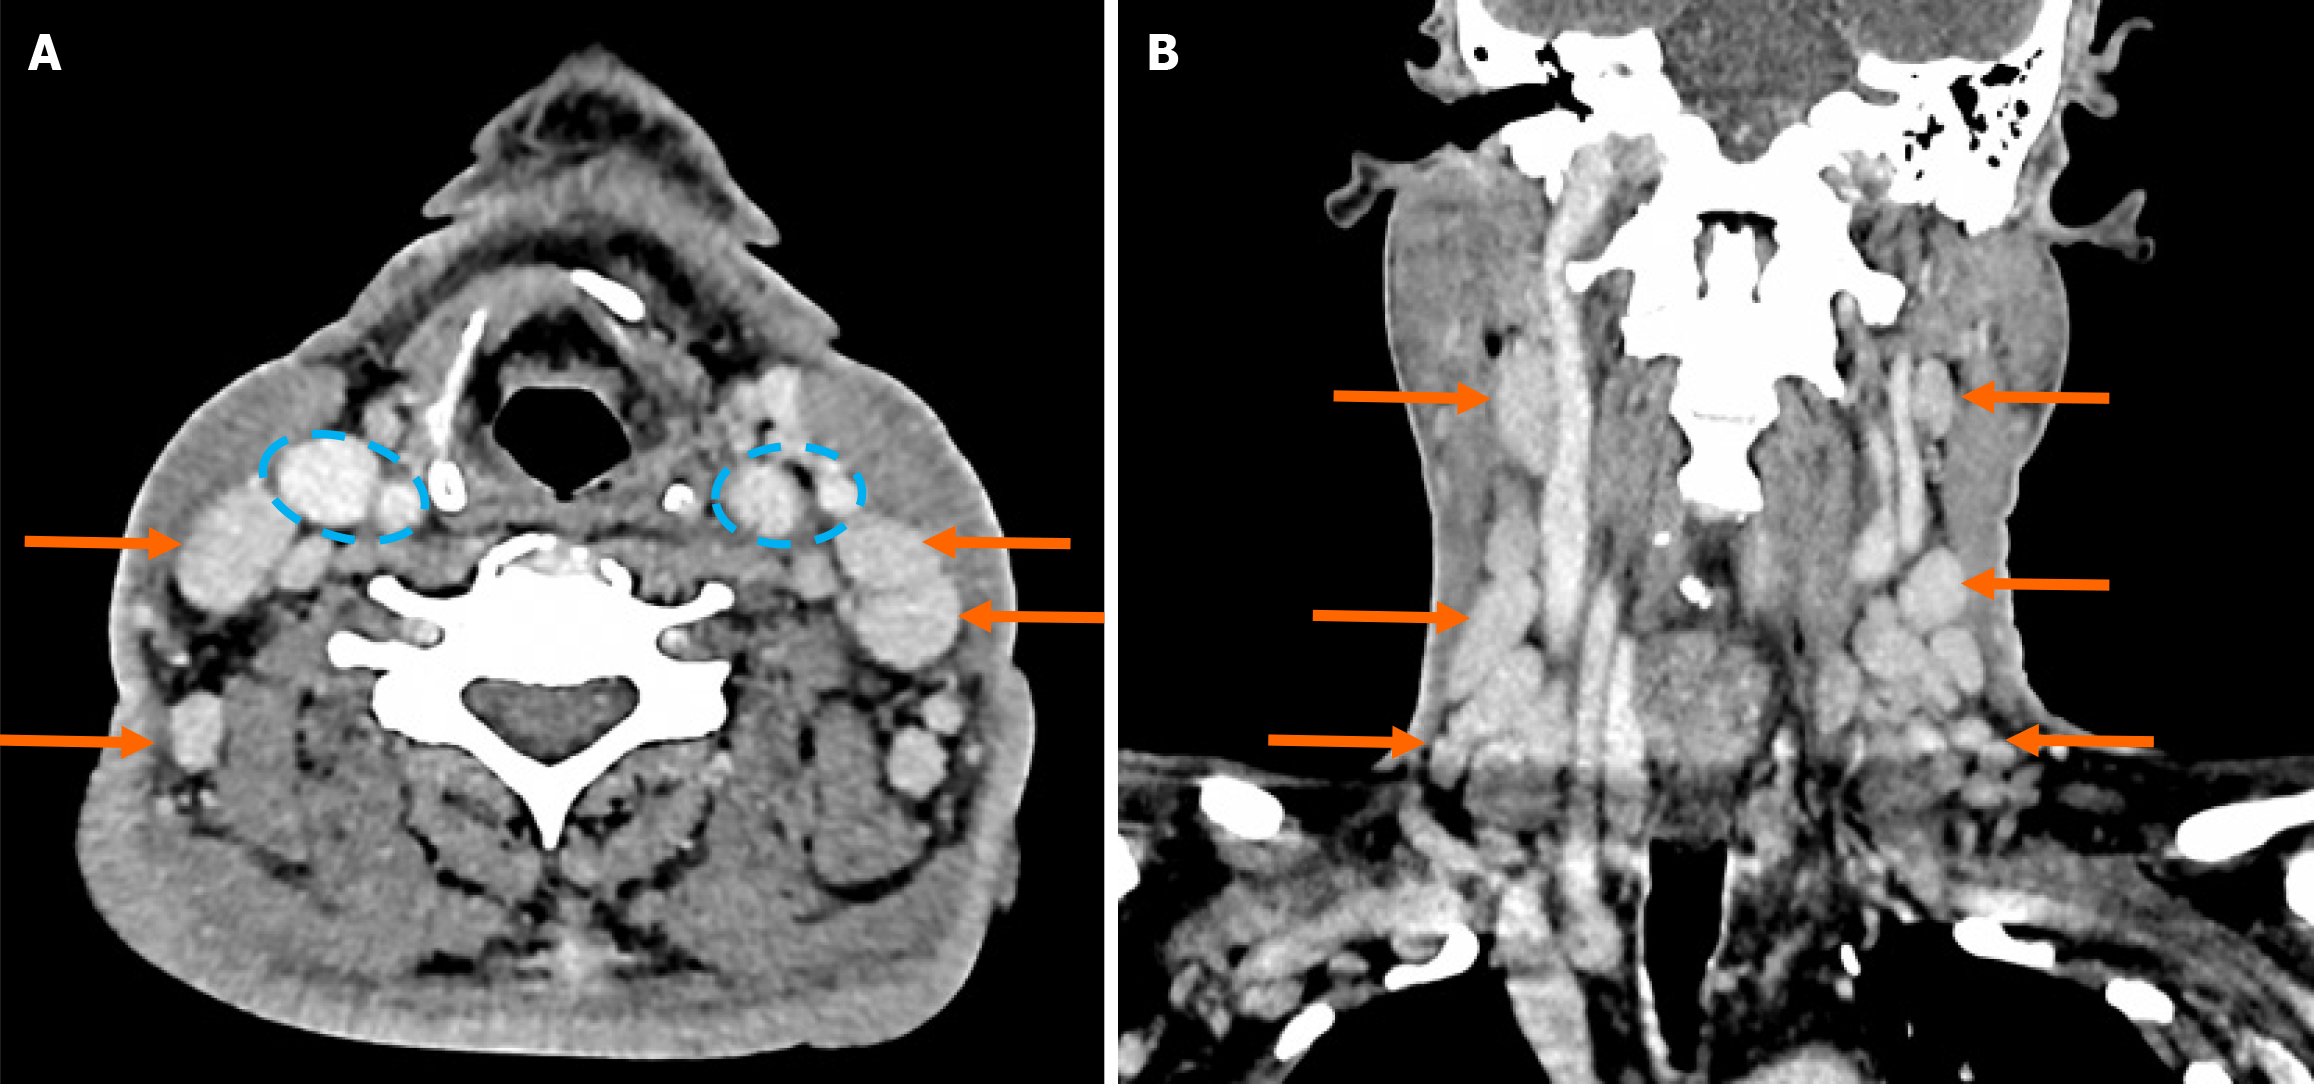

Figure 5 Contrast enhanced computed tomography neck.

A: Axial computed tomography (CT) with multiple enlarged cervical and supraclavicular lymph nodes (arrows) and patent bilateral carotid and jugular vessels are highlighted within the blue dotted lines; B: Sagittal CT with similarly enlarged nodes as mentioned (arrows).